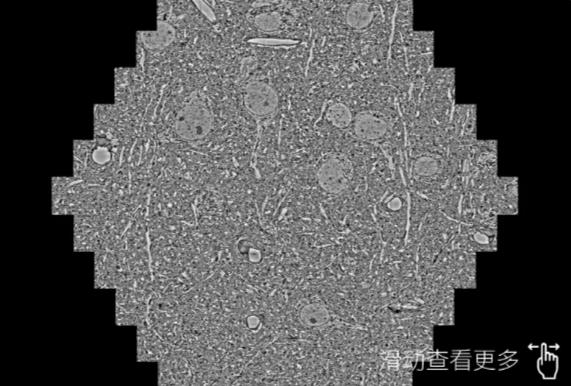

鼠脑切片。左图使用彭水蔡司彭水扫描电镜MultiSEM706对165μmx143pm面积区域成像,耗时仅需1.5秒。右图为鼠脑切片中30μm区域放大效果。样品由芝加哥大学B.Kasthuri提供。

使用蔡司高速彭水扫描电镜MultiSEM对1mm²人脑皮层组织进行高分辨成像,并对其中的各种细胞结构进行三维重构分析。左图展示了2x3mm²组织平面中锥体神经元的三维重构效果。右图显示了局部体积神经元三维重构。图像由哈佛大学chtman实验室提供,渲染图由D. Berger 制作。